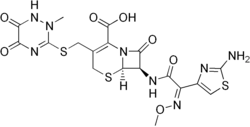

Empiric antibiotics (treatment without exact diagnosis) should be started immediately, even before the results of the lumbar puncture and CSF analysis are known. The choice of initial treatment depends largely on the kind of bacteria that cause meningitis in a particular place and population. For instance, in the United Kingdom, empirical treatment consists of a third-generation cefalosporin such as cefotaxime or ceftriaxone.[48][49] In the US, where resistance to cefalosporins is increasingly found in streptococci, addition of vancomycin to the initial treatment is recommended.[3][8][48] Chloramphenicol, either alone or in combination with ampicillin, however, appears to work equally well.[73]

Empirical therapy may be chosen based on the person's age, whether the infection was preceded by a head injury, whether the person has undergone recent neurosurgery, and whether or not a cerebral shunt is present.[8] In young children and those over 50 years of age, as well as those who are immunocompromised, the addition of ampicillin is recommended to cover Listeria monocytogenes.[8][48] Once the Gram stain results become available, and the broad type of bacterial cause is known, it may be possible to change the antibiotics to those likely to deal with the presumed group of pathogens.[8] The results of the CSF culture generally take longer to become available (24–48 hours). Once they do, empiric therapy may be switched to specific antibiotic therapy targeted to the specific causative organism and its sensitivities to antibiotics.[8] For an antibiotic to be effective in meningitis, it must not only be active against the pathogenic bacterium but also reach the meninges in adequate quantities; some antibiotics have inadequate penetrance and therefore have little use in meningitis. Most of the antibiotics used in meningitis have not been tested directly on people with meningitis in clinical trials. Rather, the relevant knowledge has mostly derived from laboratory studies in rabbits.[8] Tuberculous meningitis requires prolonged treatment with antibiotics. While tuberculosis of the lungs is typically treated for six months, those with tuberculous meningitis are typically treated for a year or longer.[31]